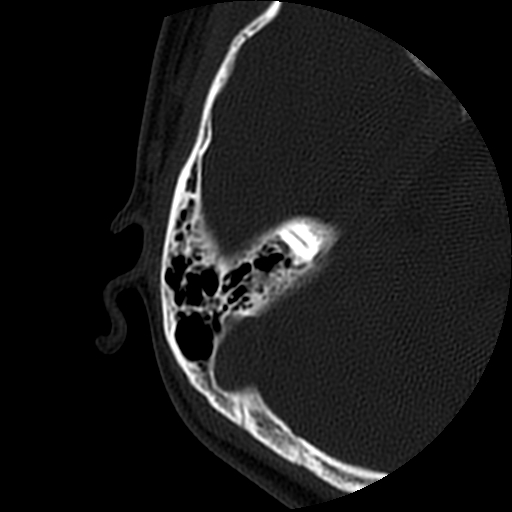

以下是引用随光逐影在2009-8-19 7:25:00的发言:[br]右侧慢性中耳乳突炎,右侧中耳腔及外耳道肉芽肿或胆脂瘤形成。